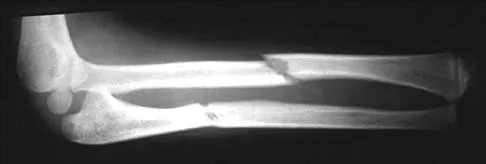

A 36-year-old recreational tennis player sustains the injury shown in Figure 16. Management should consist of

Explanation